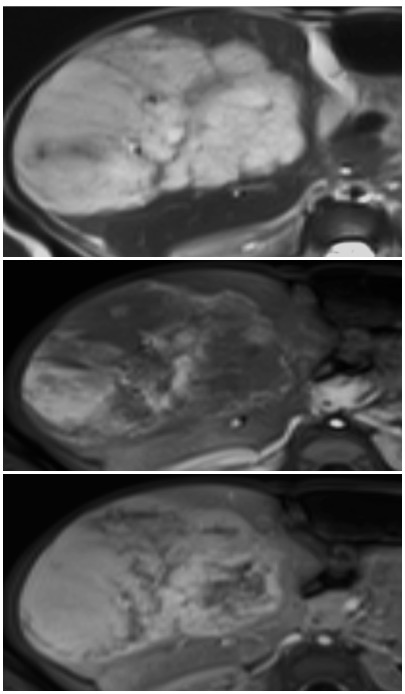

T2W, arterial and delayed post contrast images in a 3 month old demonstrate a T2 bright hepatic mass with peripheral arterial enhancement with delayed filling in, consistent with a hemangioma (infantile hemangioma is the technically correct term)